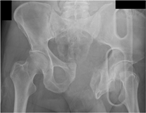

Severe pelvic fracture with profound hypotension: a case report and treatment algorithm

Chadwick J. Knight and others

Journal of Surgical Case Reports, Volume 2017, Issue 6, June 2017, rjx093, https://doi.org/10.1093/jscr/rjx093